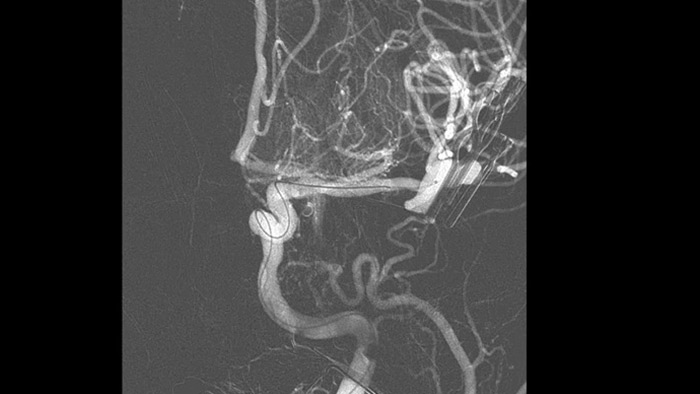

Las referencias anatómicas admiten una navegación 3D precisa

Navegación 3D precisa con SmartCT Roadmap

SmartCT Roadmap proporciona referencias anatómicas para permitir la navegación precisa de la guía, el catéter y el dispositivo al coágulo.

Confirme el éxito del tratamiento

Visualización DSA

Las visualizaciones de DSA de alta calidad le permiten evaluar si ha recuperado el coágulo completo y si se han dispersado trozos de coágulo distalmente en el cerebro. Puede verificar la restauración del flujo sanguíneo a la penumbra y verificar si hay hemorragias periprocedimiento.